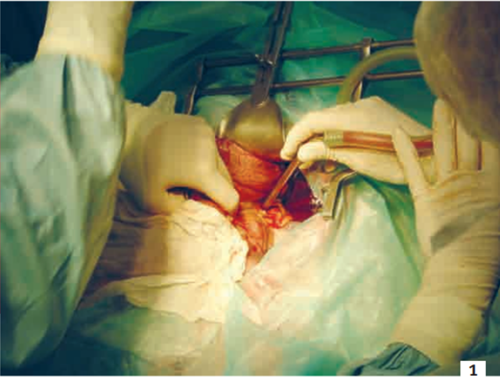

Comme pour toute laparotomie, la surrénalectomie est un acte douloureux. L’accessibilité réduite oblige l’équipe chirurgicale à pratiquer une incision large, à utiliser des écarteurs et à manipuler les tissus avoisinants (photo 1).

Ces gestes engendrent une souffrance nociceptive sévère à très sévère. Certaines complications comme la pancréatite peuvent aussi être à l’origine de phénomènes algiques intenses.

Photo 1 - Vue peropératoire d’une surrénalectomie gauche chez un chien.

Noter la taille de l’incision, la présence d’un écarteur et la manipulation des tissus mous, sources de douleur pour l’animal.

Photo : C. Bille